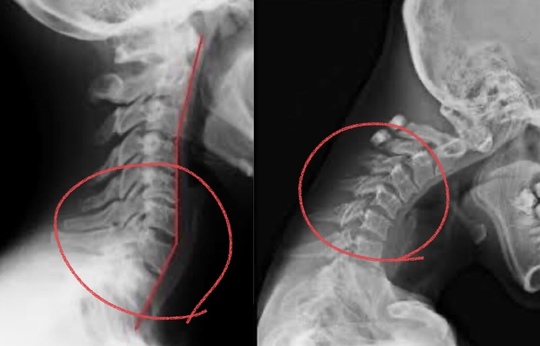

レントゲン・CT・MRIを撮って、骨や椎間板に異常があったとしても痛みを出している原因はそれ以外のところにある事が多くあります!

レントゲン・CT・MRIはとても素晴らしい検査機器です。

しかし、それらは「今のカラダの状態がどうなっているのか!!」 または、「静止画像 静止した状態」での検査方法になります。

ヒトが痛みを出すときは、動いた瞬間や動いている時に痛めることが多いです。

デスクワークでの首・肩こりの痛みが出るパターンの多くは、日常的な不良姿勢が原因になる事が多いです。

デスクワーク・スマホなどの使用により背中が丸まる。

そして頭が前に出る。頭が前に出ると

頭の重さ通常の2倍 3倍となり首の後面にある筋肉に疲労がたまり痛みを出し炎症を起こす